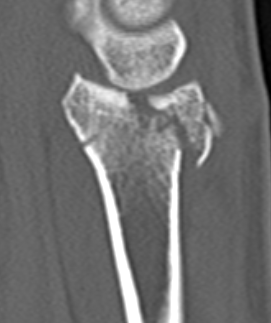

Distal radius fracture with shortening and dorsal tilt

Articular incongruency > 2 mm

Sigmoid notch disruption and DRUJ instability